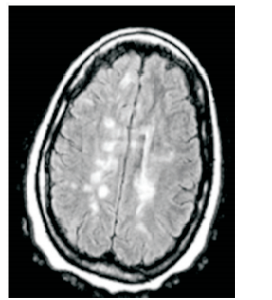

Paciente do sexo feminino, 30 anos, previamente hígida. Apresentou quadro súbito de perda da visão do olho direito com recuperação total em 15 dias. À época não foi feita nenhuma avaliação neurológica. Após seis meses, a paciente apresentou quadro de tonteira e a seguinte imagem é encontrada em sua ressonância magnética de crânio:

Com base na história clínica e na imagem, é necessário investigar qual doença neurológica?